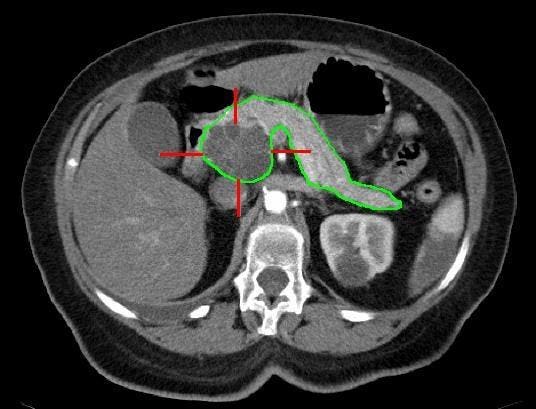

Pancreatic cancer is particularly challenging to treat due to its late-stage diagnosis and the aggressive nature of the disease. Traditional treatments like chemotherapy have had limited success, with most patients surviving less than a year after diagnosis. CAR T therapy, which has been successful in treating blood cancers, faces unique challenges when it comes to solid tumors like pancreatic cancer. The dense tissue and abnormal blood vessels of pancreatic tumors make it difficult for immune cells to penetrate and target the cancer cells effectively. Additionally, the lack of clear markers on cancer cells and the similarity between healthy and cancerous cells further complicates treatment with immune cell therapy.